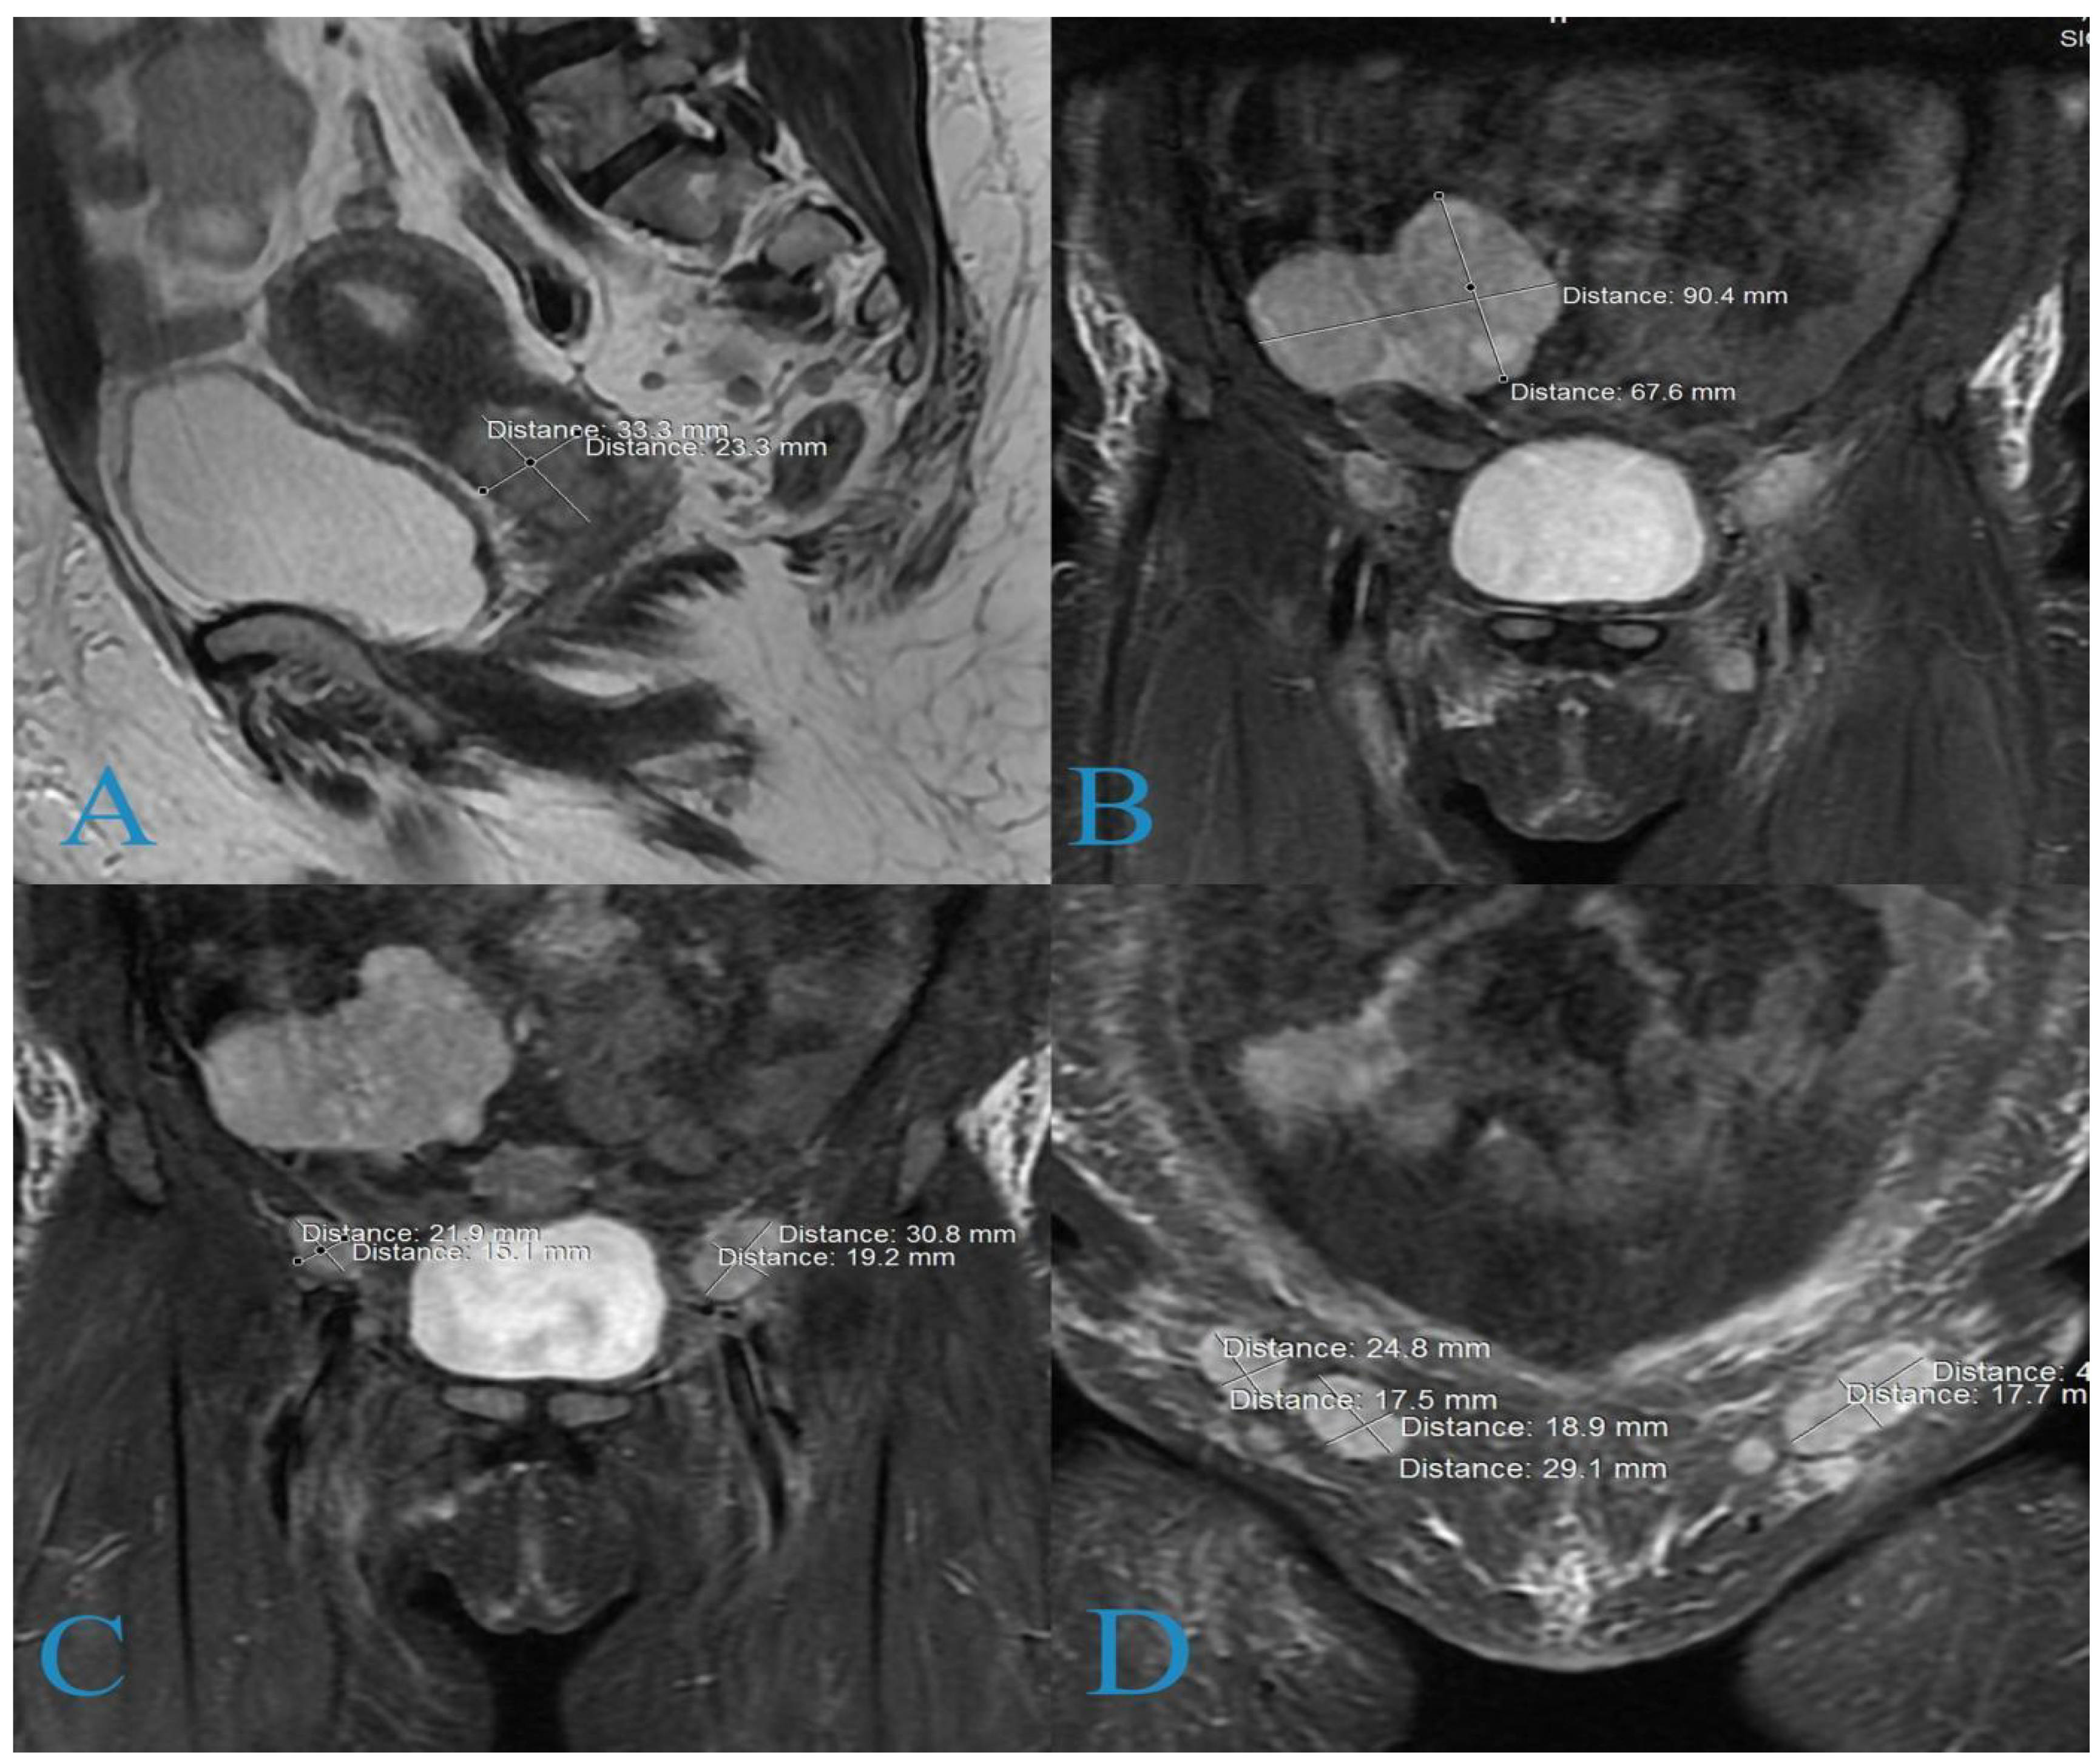

2. Case Report